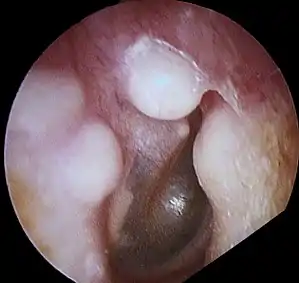

| Osteoma of external auditory meatus | |

Osteoma represents the most common benign neoplasm of the nose and paranasal sinuses. The cause of osteomata is uncertain, but commonly accepted theories propose embryologic, traumatic, or infectious causes. Osteomata are also found in Gardner's syndrome. Larger craniofacial osteomata may cause facial pain, headache, and infection due to obstructed nasofrontal ducts. Often, craniofacial osteoma presents itself through ocular signs and symptoms (such as proptosis).[1]